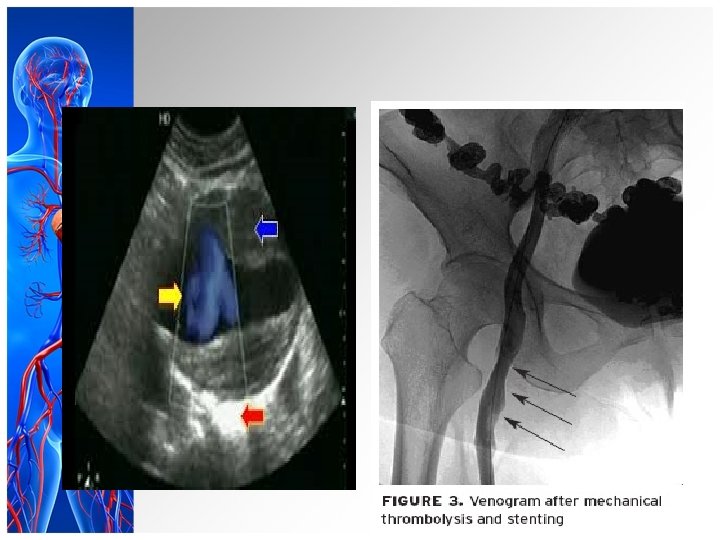

DIAGNOSTIC EVALUATION History collection Physical examination Color flow duplex ultrasound imaging D- Dimer test

Cont…. Venography CT venography MR venography

Cont… q. Bed rest q. Leg elevation q. Compression stockings q. Pharmacological measures – Heparin – Warfarin – Thrombolytic therapy

Cont… Thrombolytic therapy Eg; streptokinase, urokinase, recombinant tissue plasminogen(reteplase, alteplase)

Surgical management v. Thrombectomy- transvenous filtration device • Greenfield filter • Bird’s nest filter v. Guidelines for safe practice